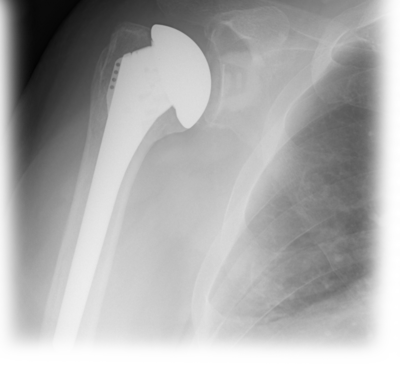

The Univers II humeral component was designed to account for anatomical variations of the proximal humerus commonly encountered by the surgeon. Variable adjustment with respect to the inclination angle, version and head offset are features critical to reconstruction of the proximal humerus. The simplified design of the Univers II humeral component allows the surgeon to adapt the humeral stem and articular surface to the position that best represents the patient’s normal anatomy. All of the adjustments can be made intraoperatively with the implant in the humeral canal. This unique feature allows more accurate recreation of the normal anatomical relationships of the shoulder joint. With anatomic restoration of the humerus and glenoid, soft tissue balancing of the rotator cuff is more accurate, allowing for improved functional outcome.